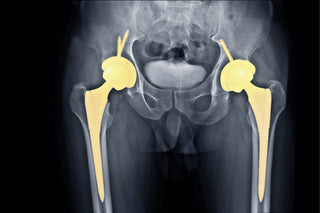

Hva gjør du når kroppen setter begrensninger? Når smerter og skader tvinger deg til å gi opp de bevegelsene som en gang var en selvfølge? Dette er historien om en...